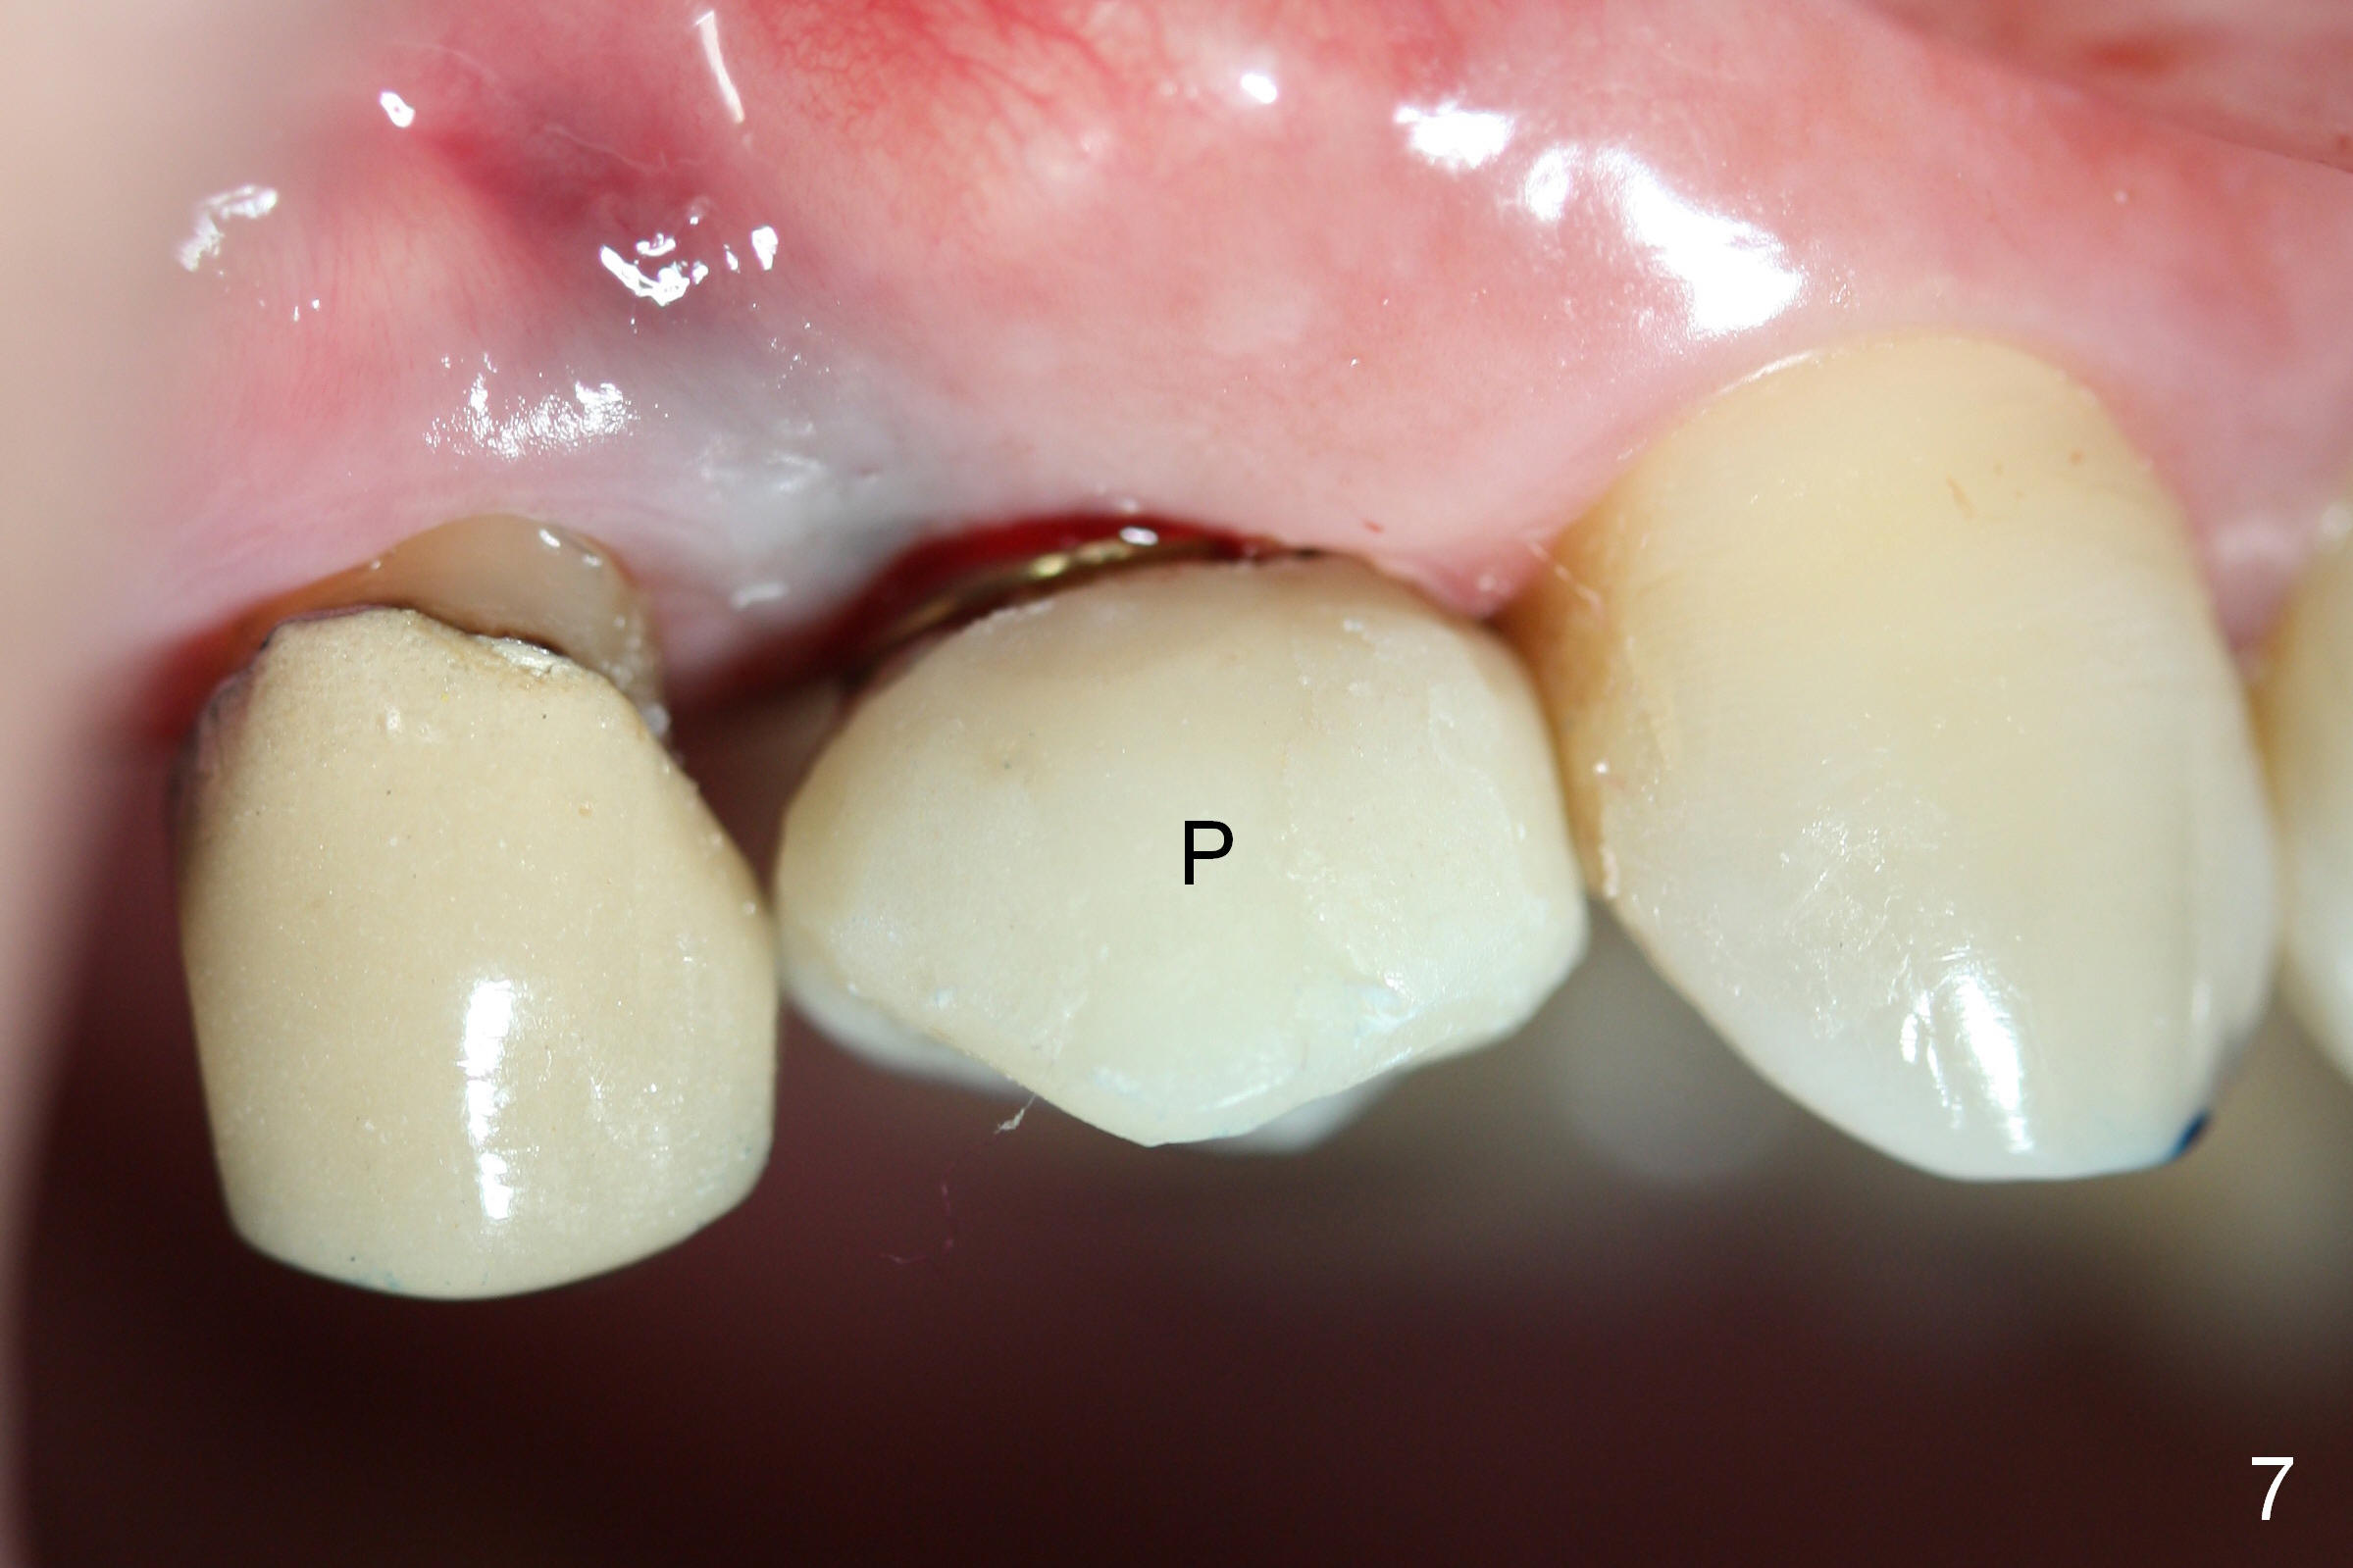

A 66-year-old man has lost several teeth (Fig.1,2). There is a particularly wide mesiodistal space for the site of #5 (Fig.1), probably due to distalization of the tooth #4 under heavy occlusion (Fig.2 arrow). A 4 mm tissue punch is used for access, followed by 1.6 mm pilot drill (Fig.3). After trajectory adjustment, a 2 mm parallel pin is inserted (Fig.4); later the osteotomy is moved distally (arrow). Finally a 4.5x14 mm implant is placed (Fig.5 I). Due to limited access, the implant is placed a little deeper than necessary; the gingival cuff of an abutment has to be longer (Fig.6 A: 5.8x4(3) mm). An immediate provisional is fabricated (Fig.7,8 P). The provisional looks wide (Fig.7). When the implant osteointegrates, limited orthodontic treatment will be done to idealize the space of #5 as follows.

The distal surface of the provisional will be reduced (Fig.9,10 D), whereas the occlusal surface will be increased (Fig.9 O). If needed, the occlusal surface of the distalized tooth #4 will be reduced (Fig.9 red area) so that there is no interference for tooth to move. Hooks will be placed on the buccal and lingual surfaces of the provisional (Fig.10 green curved lines). Power chains will be placed on the hooks and wrapped around the tooth #4. In due time, the tooth will be mesialized (Fig.11 arrow). Implants at the sites of #2 and 3 will be placed in more appropriate positions.